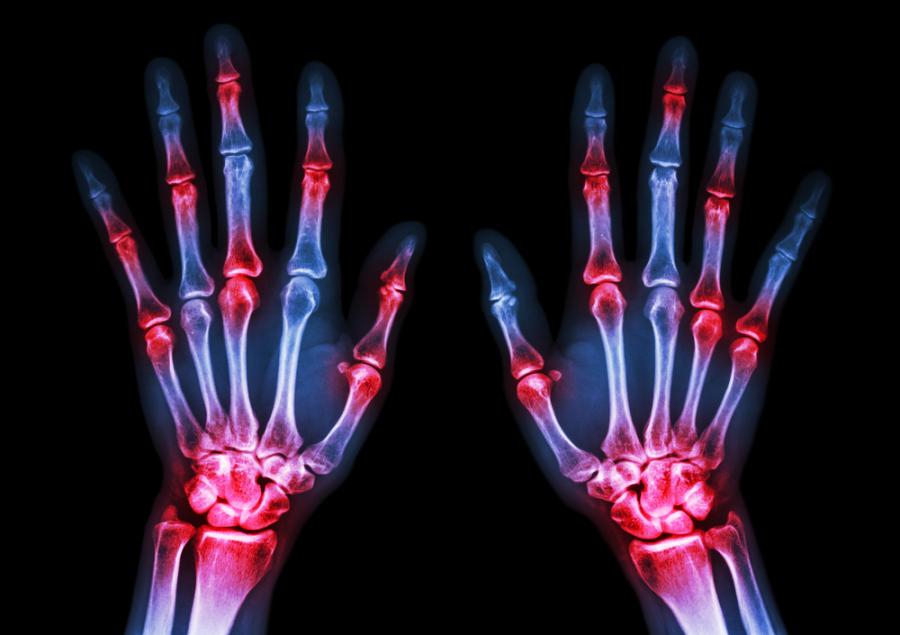

Ревматоидният артрит е автоимунно заболяване, което възниква, когато имунната система атакува собствения си организъм. Сред симптомите на състоянието са болки в ставите, скованост и умора, пише БТА. Новото лекарство, наречено пересолимаб, е моноклонално антитяло, което стимулира така наречения „протеин на програмираната клетъчна смърт“. Този протеин изпълнява ролята на спирачка на имунната система, обясни авторът на изследването д-р Ейджей Нирула. Нирула е вицепрезидент на отдела по имунология на американската фармацевтична компания „Лили рисърч лабраторис“, която финансира разработването на перезолимаб.